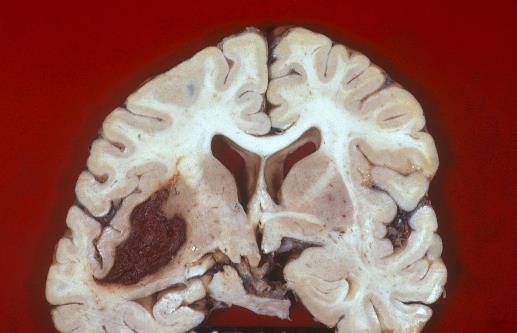

在了解脑出血的前兆之前我们先要看看什么是脑出血。脑溢血又称脑出血、发病急且进展迅速。数据显示在发生脑出血的患者中50%有先兆症状。脑溢血是指脑内微血管破裂出血是老年人的常见病好发于寒冷的冬季。常常表现为突然的一侧肢体麻木、无力或瘫痪,因此病人会在毫无防备的情况下跌倒或手中的物品突然掉地同时伴有口角歪斜、流口水、语言含糊不清或失语,严重者伴有意识障碍、大小便失禁等。病因多与高血压、动脉硬化有关具有起病急、后遗症多等特点对老人的危害很大是中老年人致死性疾病之一。